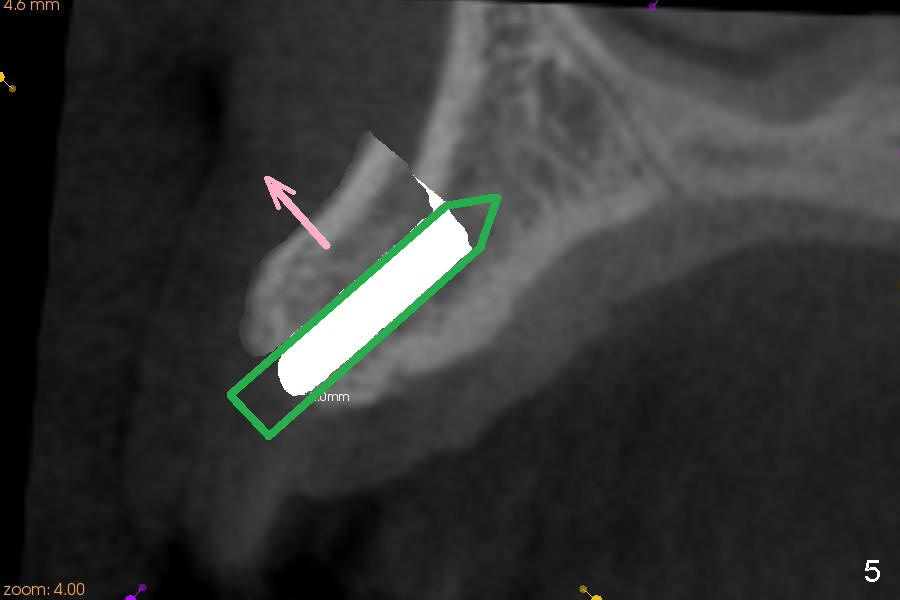

A 45-year-old lady has history of chronic periodontitis. The tooth #6 has lost several years (Fig.1). The buccolingual width decreases (Fig.2 (7mm), as compared to #11 in Fig.6 (10 mm)). Bone expansion is necessary for implantation. It should be done gently, since she is a dental phobic. First the crestal cortex is split with a surgical fissural bur (Fig.3 red line), followed by thin osteotomes (Fig.4 green line: scalpel, bone scalpels (probably until 5 or 6 mm, as indicated by Fig.1 (mesiodistal width)), bone blades (until 5.5 mm)). If the patient cannot tolerate tapping, 1.6 mm pilot drill is used at the depth of 14 mm, followed by bone expanders (probably until 2.9/3.8 using handpiece). As expanders or rounded osteotomes increases in diameter (Fig.5 green arrow), the buccal plate moves buccally (pink arrow). The bone expansion improves cosmetics as well. The implant is planned to be 4.5x14 mm, bone level. Angled abutment is expected. In contrast, immediate implant prevents buccal plate atrophy and avoids bone expansion. How is the surgery?